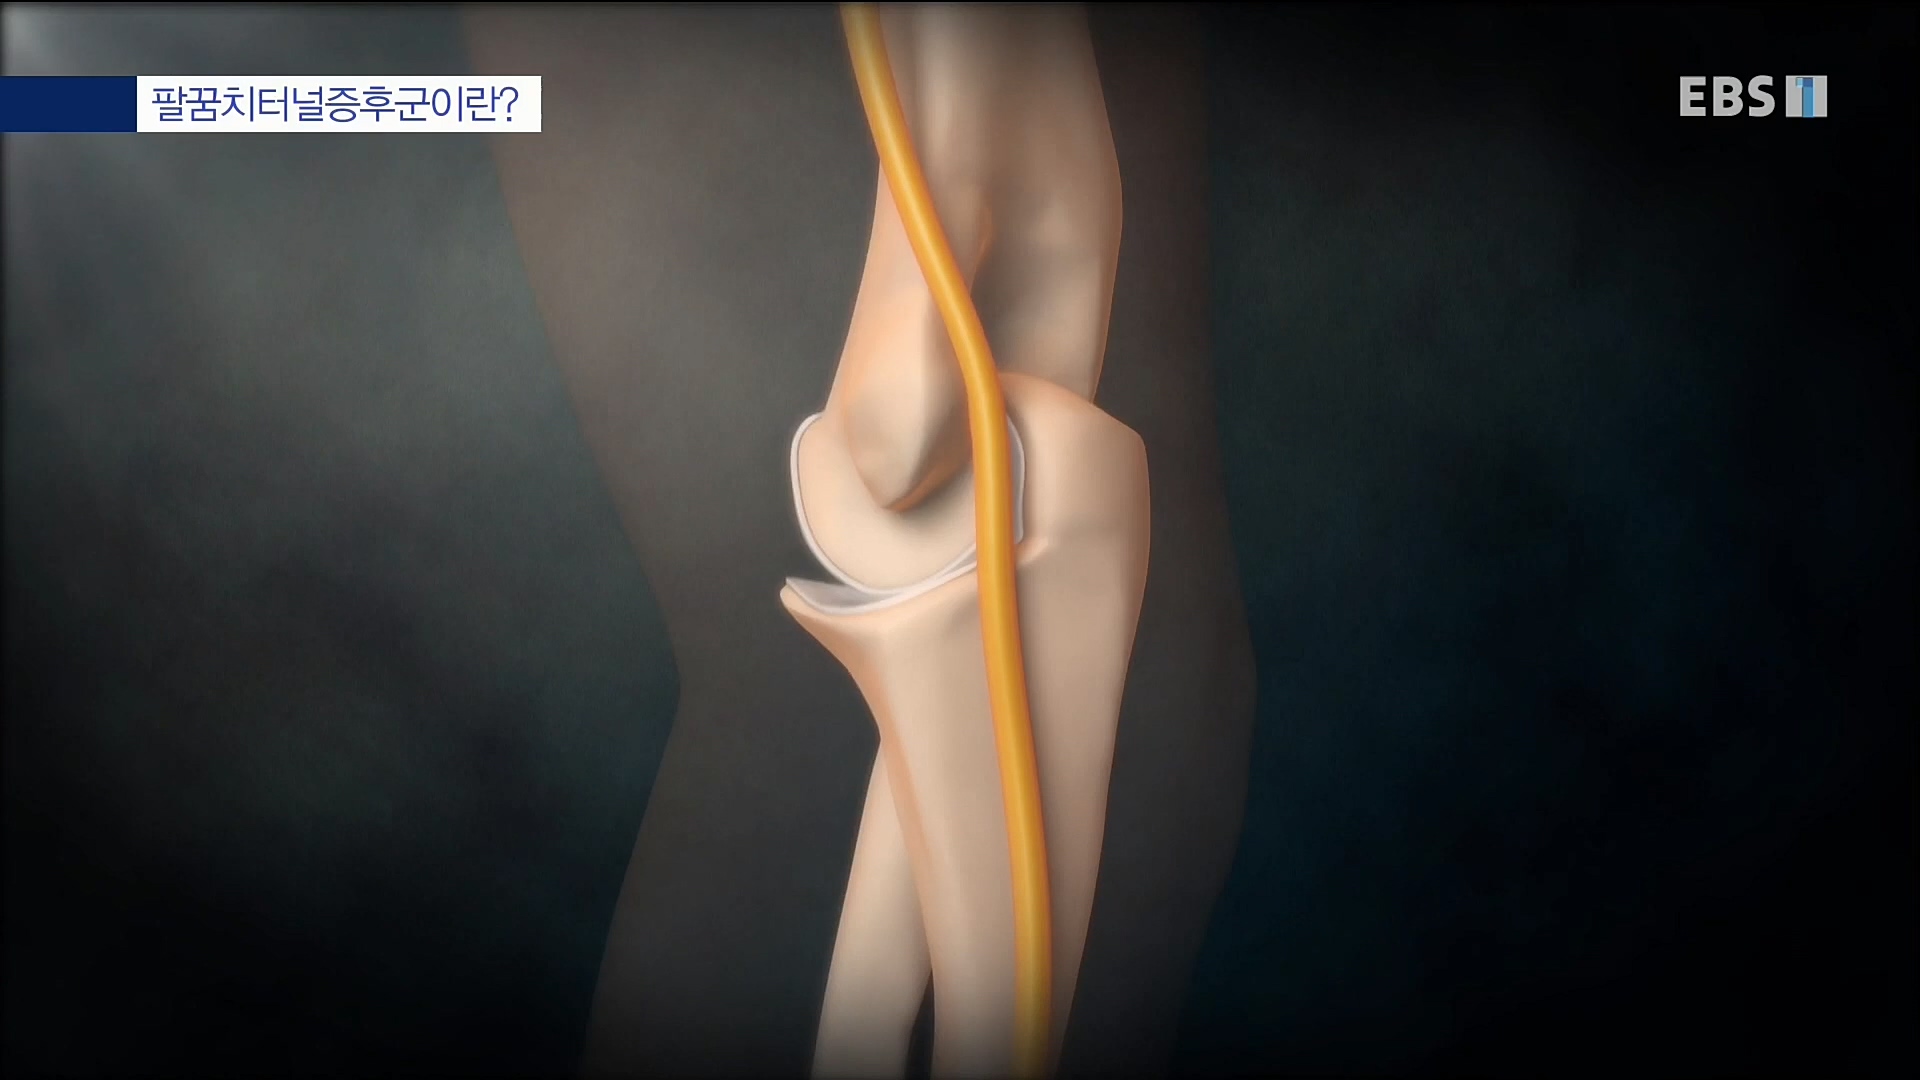

명의' 최윤락 교수와 함께 손목터널증후군, 드퀘르벵병, 팔꿈치터널증후군, 흉곽출구증후군, 손목 물혹(결절종), 방아쇠수지 등 손과 팔에 생길 수...

이날 EBS 명의 '손이 보내는 경고, 저림과 통증' 편에서는 정형외과 전문의이자 수부외과 세부전문의 최윤락 교수와 함께 손과 팔에 생길 수 있는...